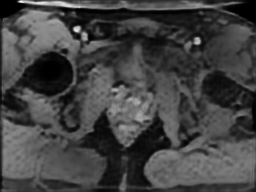

Tables 1 and 2 show our quantitative results: PSNR between the style (image we want to transfer style from) and generated image, SSIM and MS-SSIM between the content (image we want to take structure from) and generated image and finally, our proposed weighted SSIMs. For each style transfer direction and metric, our method consistently outperforms the other approaches. Figures 2 and 3 qualitatively highlight the good results of our method on 2D and 3D datasets. In addition, quantitative results on both figures show that our proposed metric preserves qualitative ordering of results for both style and content. In comparison, metrics such as SSIM struggle to accurately correlate to visual results.

Qualitative evaluation shows that the proposed method leads to sharper images, better content preservation, better localised CE and realistic MRI appearance. Quantitatively, we outperform the other algorithms with each metric, for each style transfer direction. While we expected that adding CE to images would be an easier task than removing CE, we found that for both tasks the method exhibits similarly performing quantitative and qualitative results. The results for style transfer with the kidney data show that when there is clear CE, it is easier to perform style transfer in both directions. However, when style transfer is performed on the prostate data, the model struggles in comparison to the kidney data. This may be due to the enhancement of the prostate being less defined than the kidney data. In figure 3(b), we can see the prostate with CE. Compared to figure 2(b) showing kidneys with CE, it is harder to determine the edges. The two original images shown in figures 3(a) and 3(b) are clear and easy to see some edges of prostate, in other images, it is harder to see the edges of the prostate.